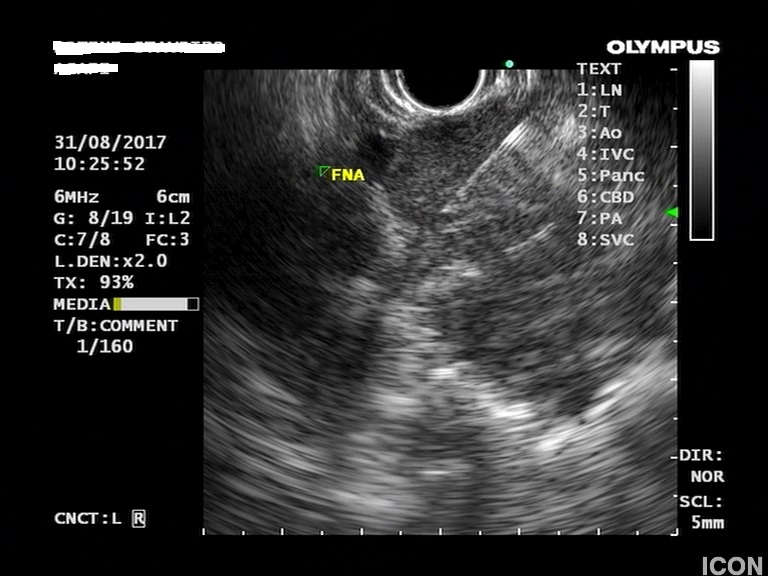

Έγινε βιοψία με λεπτή βελόνα 22g (FNA) και αναρροφήθηκε πλήρως η κύστη της κεφαλής. Οι βιοχημικοί δείκτες του υγρού της κύστης ήταν: CEA 467, αμυλάση 1550.

Λήψη υγρού με λεπτή βελόνη (FNA)